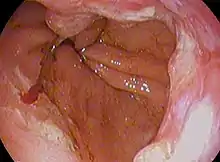

| Endoscopic image of an esophageal adenocarcinoma | |

Endoscopic image of Barrett esophagus – a frequent precursor of esophageal adenocarcinoma